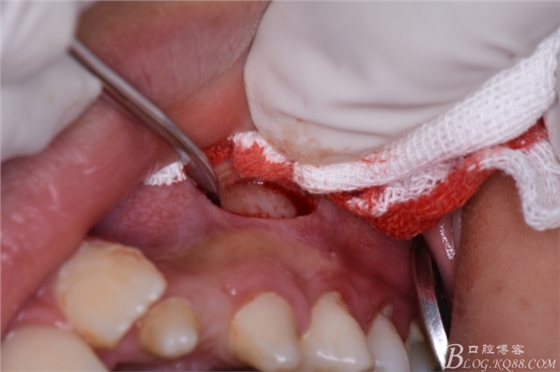

圖7.在24根尖區(qū)的前庭溝黏膜處垂直進(jìn)刀

圖8.做凸面朝向齦方的弧形切口

圖9.翻瓣、暴露出骨面